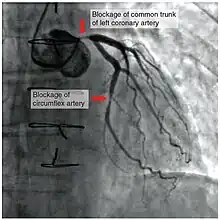

To diagnose a coronary occlusion, a doctor may view a patient's medical history, or perform a coronary angiography; a doctor will stick a catheter into the wrist or groin, lead it to the heart, and inject a liquid for X-ray imaging.[4]

To assist in a diagnosis, healthcare providers may also order a electrocardiogram (ECG or EKG), coronary calcium scan, stress test, cardiac magnetic resonance imaging (MRI), cardiac positron emission tomography (PET), invasive coronary angiography, and/or coronary CT angiography.[11]